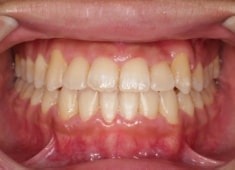

治療後(2年1ヶ月後)

反対咬合の治療は、FX(フェイシャルアキシス)が開きやすいのですが、治療後も良好な値を保つことができました。FXがあまり開きすぎると、咬合力が落ちてしまいます。

下顎の右側への偏位は解消されました。